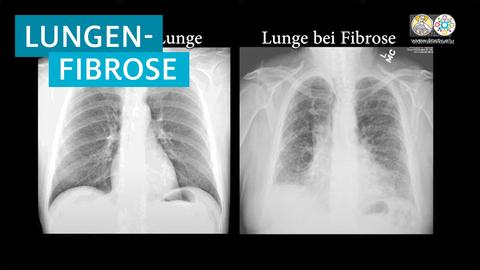

Mit einer Messung des Lungenvolumens und einer Blutgasanalyse beurteilen wir die Lungenfunktion. Die Röntgenaufnahme der Lunge und die Thorax-Computertomografie ergeben Bilder der Lungensstruktur. Sind die Untersuchungen unauffällig, können wir eine Lungenfibrose ausschließen. Gibt es auffällige Veränderungen, ist es für die Behandlung wichtig, die Ursachen zu klären.

Mit Hilfe von Lungenvolumenmessungen und Blutgasanalysen kann die Lungenfunktion beurteilt werden. Röntgenaufnahmen oder Computertomografien des Thorax liefern Bilder von der Struktur der Lunge. Sind diese Untersuchungen unauffällig, kann eine Lungenfibrose ausgeschlossen werden. Bei auffälligen Veränderungen ist es wichtig, die Ursachen zu klären, wofür eine Bronchoskopie (Lungenspiegelung) durchgeführt wird. Dabei wird unter Narkose ein flexibler Katheter mit einer Mini-Kamera durch den Mund in die Atemwege geschoben, um die Schleimhäute der Luftröhre und Bronchien zu untersuchen. Möglicherweise werden Gewebeproben entnommen, die im Labor feingeweblich untersucht werden.

– Röntgenaufnahme der Lunge: Eine Röntgenaufnahme kann erste Hinweise auf eine Lungenfibrose liefern. Dabei werden Bilder der Lungensstruktur erstellt.

– Thorax-Computertomografie (CT): Die CT ermöglicht detailliertere Aufnahmen der Lunge und kann spezifische Anzeichen für eine Fibrose zeigen. Sie wird oft in Kombination mit einer Perfusions-Szintigraphie durchgeführt, um die Durchblutung der betroffenen Areale zu beurteilen.